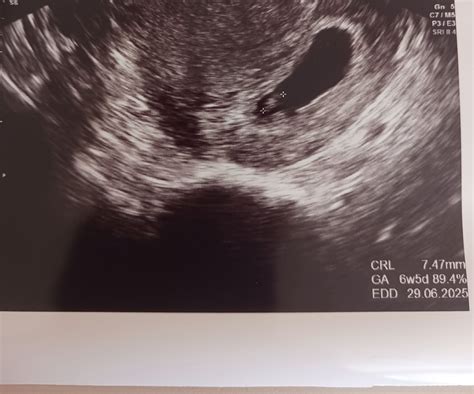

- Prvý ultrazvuk: Zvyčajne medzi 6. - 8. týždňom, potvrdí vitalitu bábätka, určí gestačný vek a početnosť tehotenstva.

V 5. týždni tehotenstva dochádza k veľkým hormonálnym zmenám, ktoré sa prejavujú precitlivenosťou. Embryo, ktoré je v tomto štádiu asi 2 mm veľké, si začína vyvíjať jednoduché srdiečko a obehový systém. V 6. týždni začína biť srdiečko plodu s frekvenciou približne 100-130 úderov za minútu. Embryo je veľmi citlivé na vonkajšie vplyvy. V 7. a 8. týždni sa vo vývoji dejú doslova divy - formuje sa nervová sústava, základy končatín, začína sa vyvíjať sluch a zrak. Embryo narastie z 2 na 16 milimetrov. Hlavička embrya je neprimerane veľká kvôli nepretržitému vývoju mozgu. Na konci 8. týždňa sa embryo nazýva plod a môže dosahovať dĺžku 16 mm.